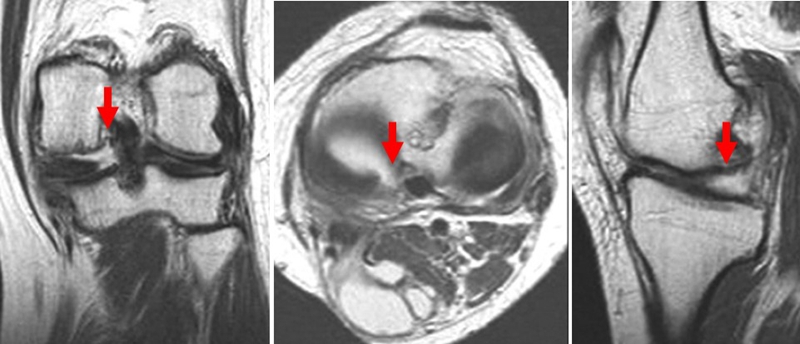

膝关节自发性骨坏死(spontaneous osteonecrosis of the knee,SONK)是指发生于股骨内侧髁负重面深层、原因不明的局部骨坏死,也可发生于股骨外侧髁或胫骨平台,在1968年由Ahlback等首先描述。

病理显示软骨下不完全骨折或局灶性软骨下骨坏死

影像学分及期

X线+MRI:通过测量正位X线片和MRI判断坏死区域的大小。

目前SONK诊断最常用的分期方法是1979年Koshino提出的分期法。Koshino分期基于临床和影像学的结果,将SONK分为四个阶段:

Ⅰ期:患者有膝关节症状,但影像学正常;

Ⅱ期:X线显示负重区变平,软骨下信号升高,周围有骨硬化;

Ⅲ期:受影响区域扩大和软骨下塌陷;

Ⅳ期:病变周围骨硬化和髁突周围骨赘形成的退行性阶段。

1979年Koshino分期